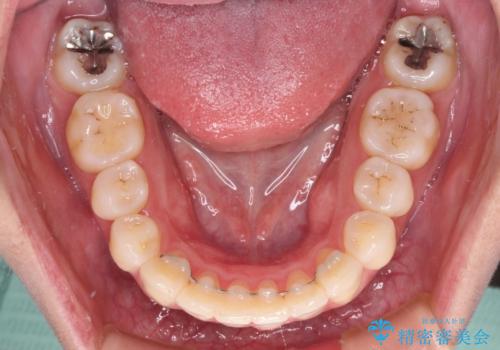

- 抜歯矯正の後戻りで前歯が突出してきていることを気にして来院された患者様です。

口元の突出感を改善するにあたり、抜歯矯正は行うことができないため、奥歯の後方移動とIPR(歯と歯の間を削る)により達成することとしました。

再度後戻りしたときに対応しやすいよう、インビザラインにて矯正治療を行うこととしました。

しっかりと装着時間を守り、ゴムかけにも協力していただいたので、口元を引っ込めることができました。